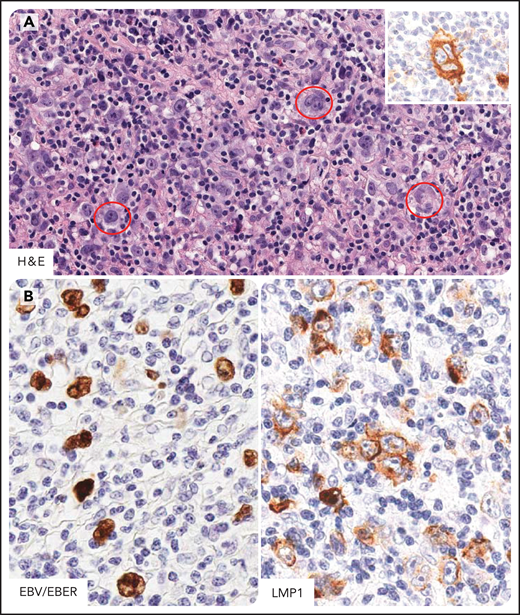

Burkitt lymphoma in individuals infected by HIV. Burkitt lymphoma with plasmacytoid differentiation; phenotypically, the tumor cells express B-cell antigens including CD20, CD10, and BCL6 and are consistently negative for BCL2. The proliferation index is very high, approximately 100%. (A) A homogeneous proliferation of medium-sized tumor cells displays a cohesive pattern. Tumor cells show round nuclei, multiple nucleoli, and small basophylic cytoplasm. Immunoblastic-like tumor cells (in the red circle) with larger nucleoli are also seen. Tumor cells typically express CD10 with membranous staining pattern and BCL6 with nuclear staining pattern. (B) Burkitt lymphoma involving capsular and extranodal tissues (arrows; i) and a hyperplastic lymphoid follicle within a reactive hyperplastic lymph node (ii). The extranodal pattern of tumor infiltration is confirmed by Ki-67 staining. H&E, hematoxylin-eosin stain; CD10, BCL6, and Ki-67 immunohistochemistry, hematoxylin counterstain. Original magnification, ×200. Images were taken using a Nikon Eclipse 80i microscope with a Plan Fluor 20×/0.75 objective and Nikon digital sight DS-Fi1 camera equipped with control unit-DS-L2. Images were processed using Adobe Photoshop CS2 V9.0.